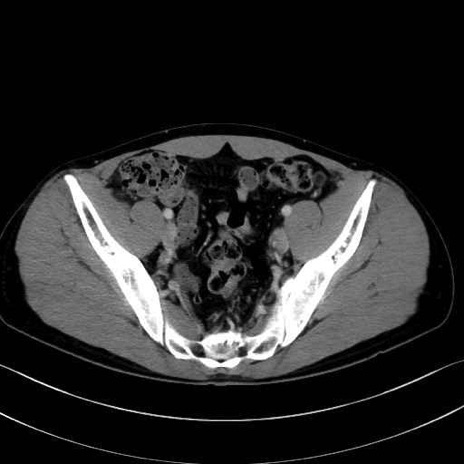

内閉鎖筋(obturator internus) のCT画像の解剖

内閉鎖筋 (Obturator internus)